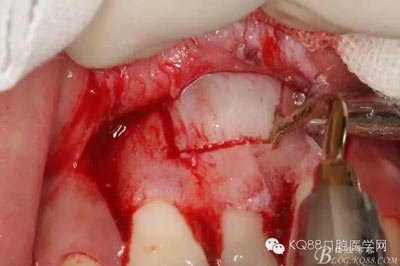

圖11.掀開(kāi)骨壁。摘除牙瘤及牙囊組織

圖12.摘除囊壁后,暴露出21的切端

圖13.超聲骨刀清理周?chē)M織,21有Ⅰ°松動(dòng)

圖14.牙冠周?chē)鷿B血多,無(wú)法粘結(jié)托槽。位置也高,隨與家屬溝通,暫時(shí)保留乳Ⅰ。待21初步穩(wěn)定,再考慮正畸牽引

圖15.輕輕的把21牙冠牽引至乳Ⅰ根尖方向,并擺正牙冠位置。(拔苗助長(zhǎng))